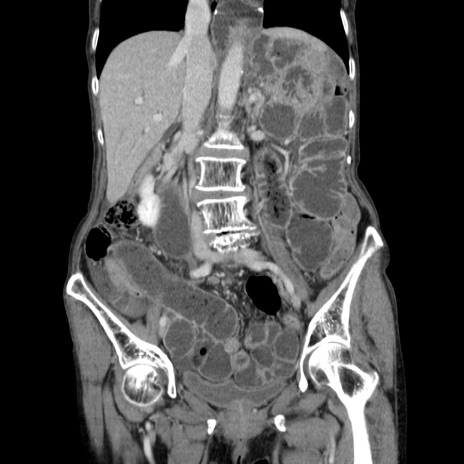

症例25(冠状断像)

【症例】80歳代女性

【主訴】胸のつかえ感

【現病歴】約9時間前に食後から胸のつかえた感じあり、嘔吐あり、来院。

【既往歴】胃癌(全摘)、胆摘、虫垂炎

【身体所見】心窩部に圧痛あり、反跳痛なし。

【データ】WBC 5700、CRP 0.05